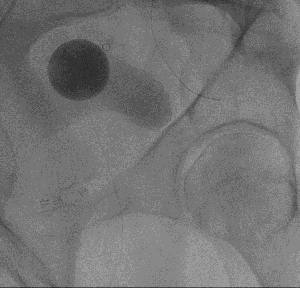

Overall, the procedure involves shrinking the prostate by treating its blood vessels. An interventional radiologist gains access through a small incision in the upper thigh or the wrist. From there, small particles are injected into the prostate to slow the blood flow to the gland, causing the prostate to shrink. Relief from BPH symptoms occurs in the following weeks and months. It is a relatively painless procedure using conscious sedation. After the procedure, UCSF Radiology follows up with patients at one, six and 12 months.